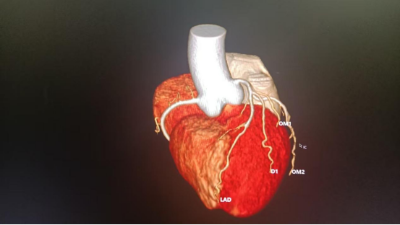

该系统的高分辨率成像技术可清晰显示亚毫米级病变,对早期肺癌、冠状动脉斑块、微小肿瘤等检出率显著提升,使“早发现、早干预”成为可能。结合智能定量分析功能,为肿瘤良恶性鉴别、心血管风险评估提供客观数据支持。